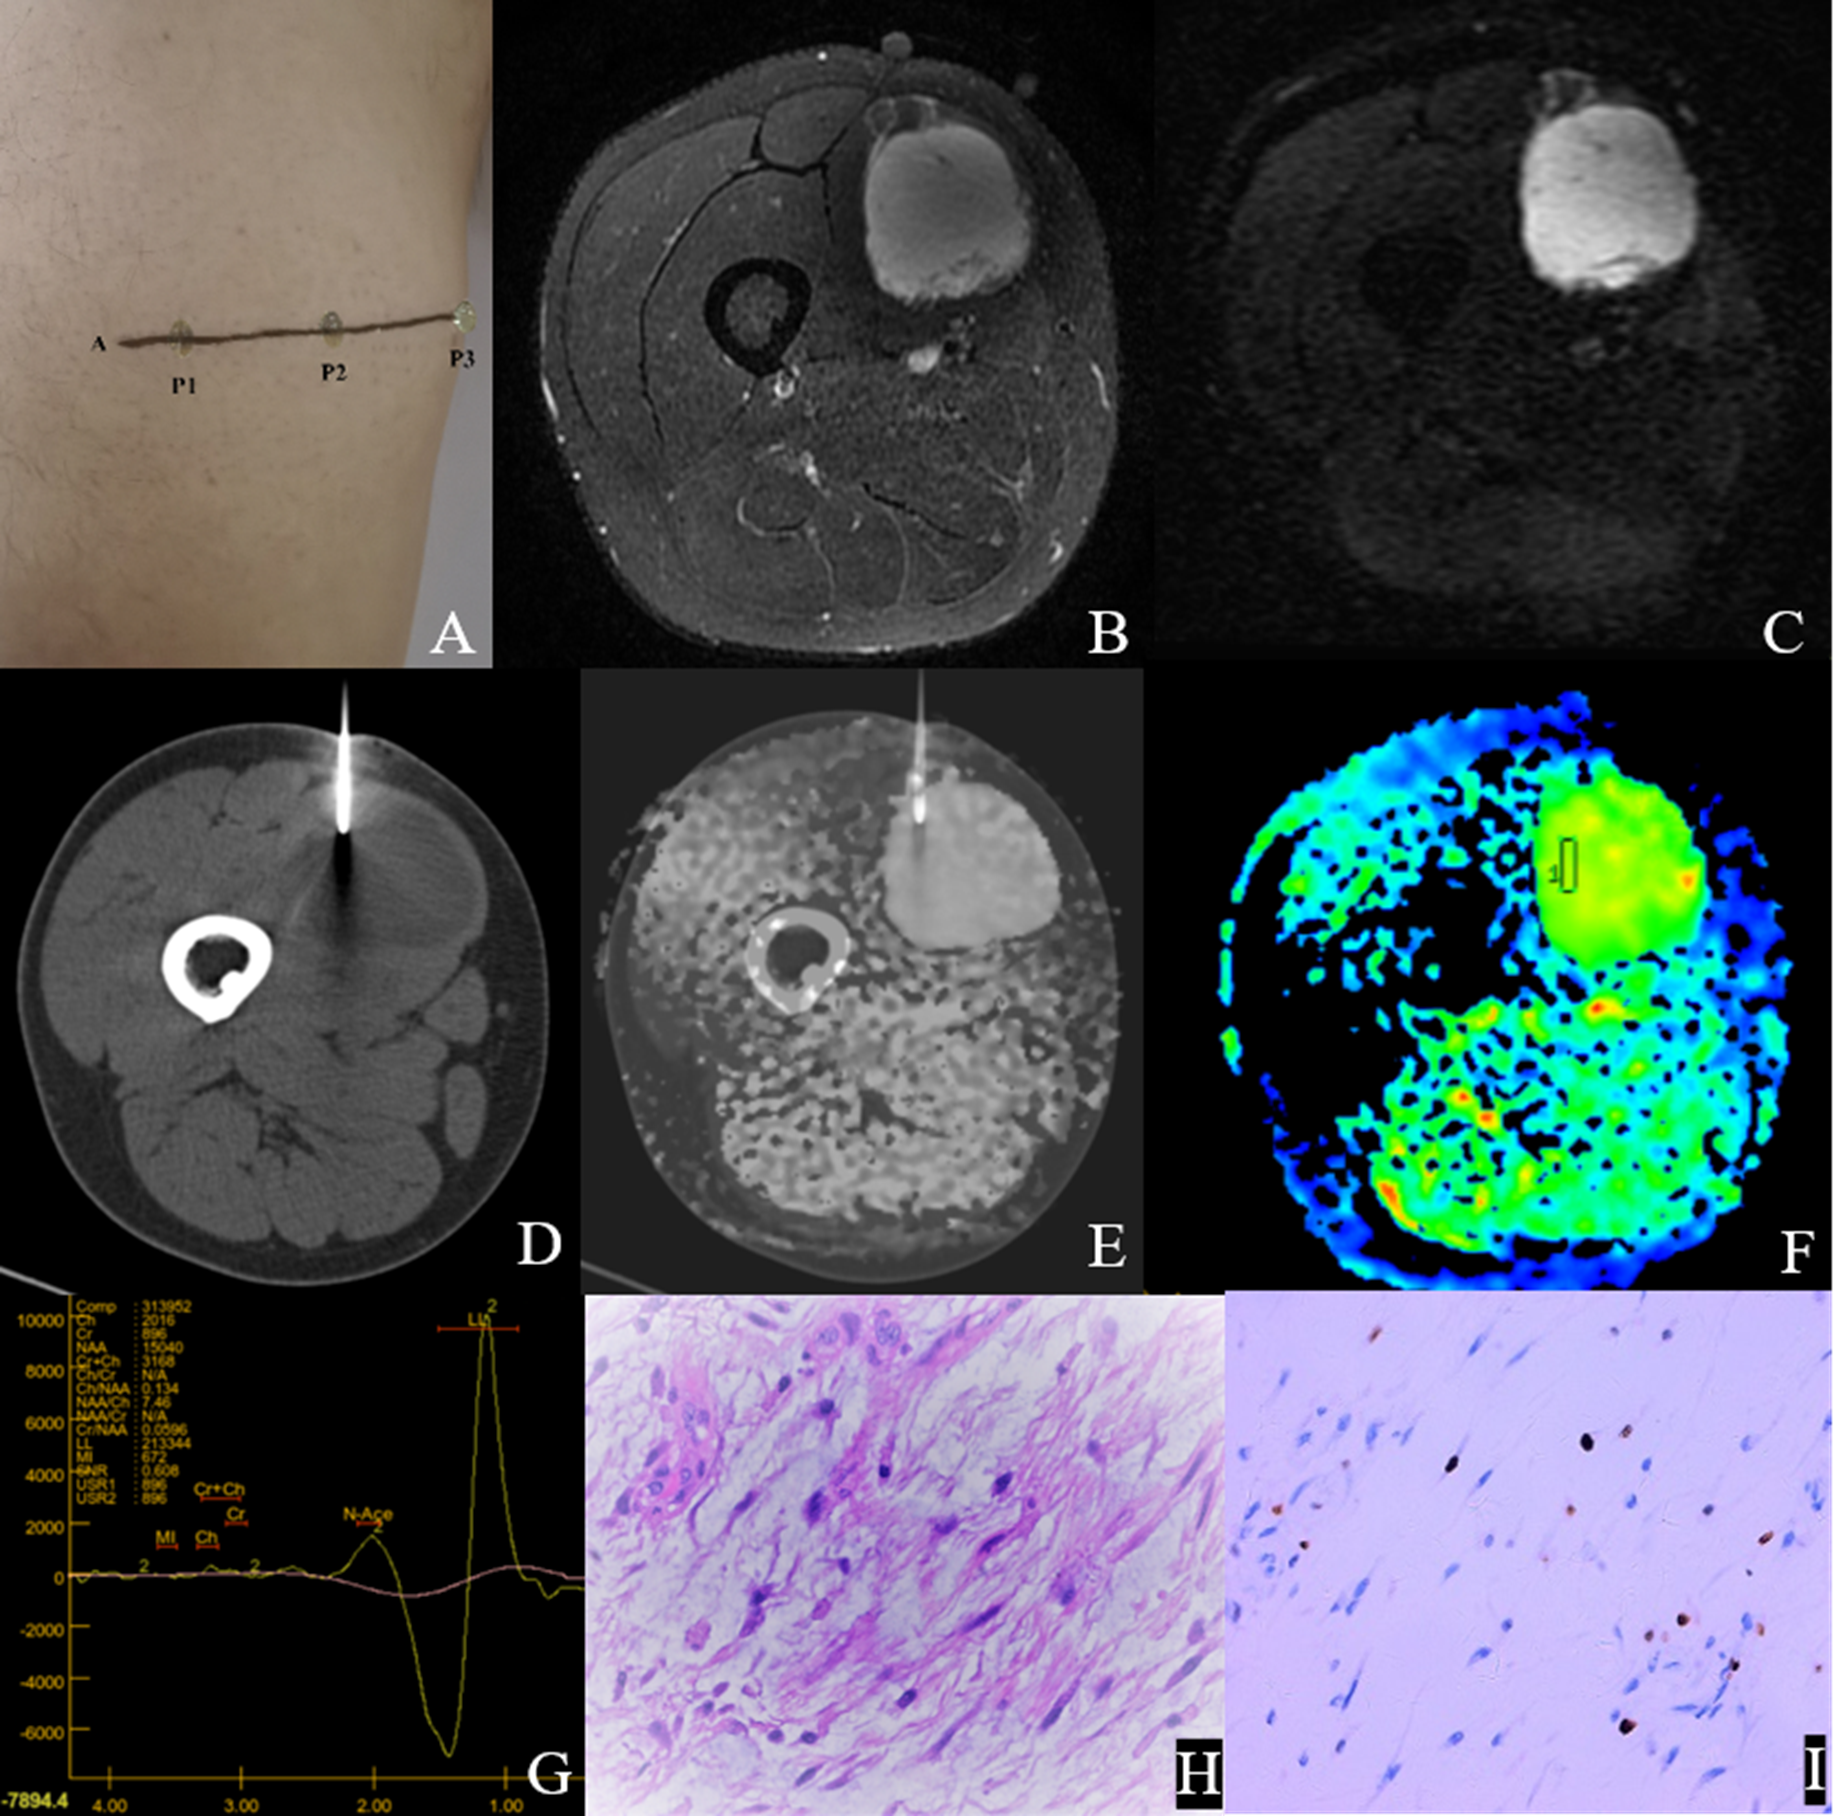

Figures 4 and 5 show the features of the CT-MR fusion registration images, pathological diagnosis, and Ki-67 LI images of the histologically confirmed pleomorphic leiomyosarcomas and myxofibrosarcomas.

Figure 5. Male,35Y, Myxofibrosarcoma of the right calf, G1. (A) Body surface positioning marks before MRI examination; (B, C) Targeted slice, chosen by Axial T2WI-FS and ADC image; (D) CT guided biopsy at target slice; (E) CT-MRI image fusion at target slice; (F) Draw ROI to obtain DWI quantitative parameters, ADCmin: 3.280×10–3 mm2/s, ADCmean: 3.370×10–3 mm2/s; (G) 1H MR spectrum, Cho/Cr:2.25; (H) Histological images of biopsy specimens, Grade3, HE×200; (I) Ki67 index 10%.